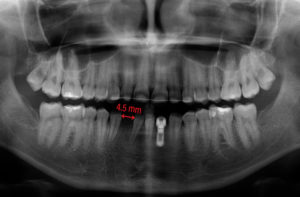

- Fig. 1 – Agenesia dell’incisivo laterale inferiore. Dopo il trattamento ortodontico lo spazio interdentale era di soli 4,5 mm. Si è pianificato l’inserimento di un impianto Leone 2.9

- Fig. 2 – Per via dello spazio molto limitato si è optato per un posizionamento sottocrestale dell’impianto

- Fig. 4 – Ortopantomografia dopo la consegna e applicazione di un retainer ortodontico